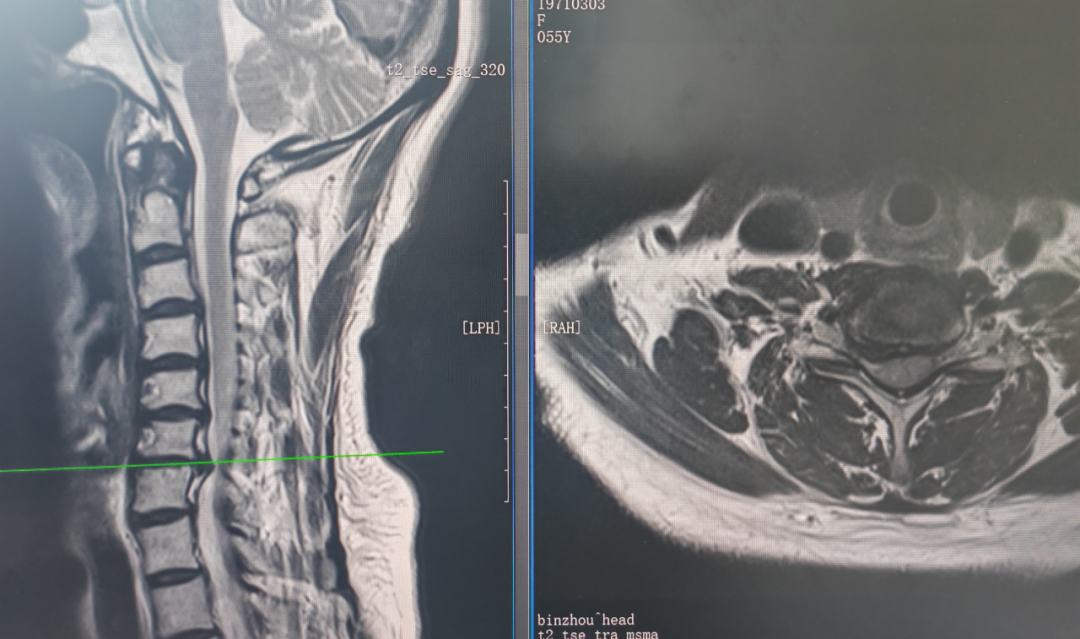

患者苑某(化名)因颈后及右肩关节疼痛不适,放射至前臂,伴抬肩功能受限,手指麻木不适,多方求医无果后来院。经详细检查和颈椎及肩关节核磁共振成像(MRI)显示,确诊为颈椎间盘突出为主要问题,压迫神经根,确诊为神经根型颈椎病。